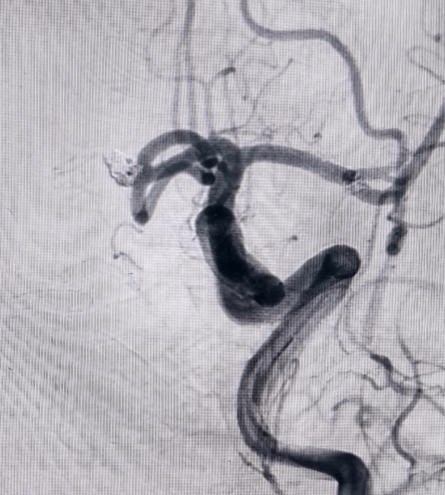

对于非责任动脉瘤的处理,医生们更是展现出专业与耐心。9个月前,患者动脉瘤破裂出血,当时造影发现2处动脉瘤,术中优先处理责任动脉瘤,待患者身体恢复后择期处理非责任动脉瘤。此次处理非责任动脉瘤,手术中造影,发现责任动脉瘤栓塞术后复发(3月前复查尚无),医生们当机立断,同期处理两个动脉瘤,省钱的同时,也成功为患者解除隐患。